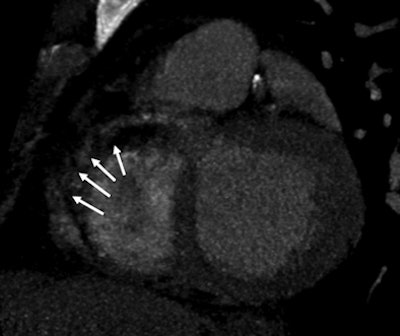

| A 51-year-old man with history of diabetes mellitus presented with typical angina. Above, curved multiplanar reformatted cardiac CT angiographic image read before perfusion shows prominent motion artifact in right coronary artery (arrows) that persisted through all cardiac phases. Below, thick short-axis CT perfusion image at midventricular level shows perfusion defect (arrows) during stress CT perfusion in the inferior and inferolateral segments that is partially reversible during rest CT perfusion. Bottom, reference-standard invasive angiogram findings confirm the presence of severely stenotic lesion in right coronary artery (arrow) that was seen at postperfusion cardiac CTA image reading. Images republished with permission of the Radiological Society of North America. |